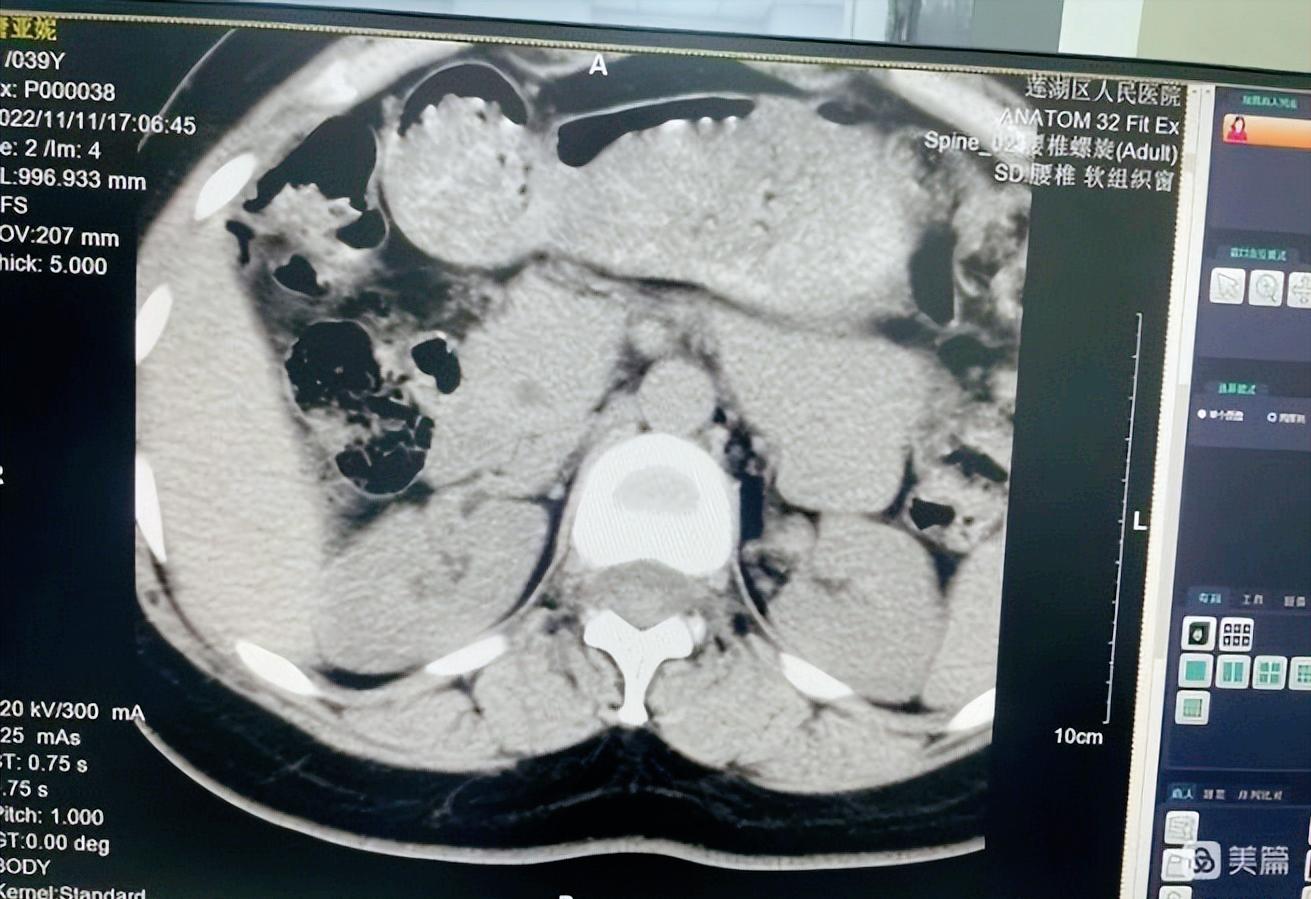

11月11日,医院10余名职工主动报名上机,给操作人员试机检查、为工程师设置检查参数、调试图像质量提供数据,使CT以最佳的运行状态为广大患者服务。

11月15日,CT正式开机启动,开机当天5名患者做了CT检查,患者表示非常满意。CT的投入使用标志着莲湖区人民医院CT服务项目的全面开展,极大程度上方便辖区以及周边群众,既减轻了患者的经济负担,也为临床疾病做出快速诊断,使患者能够得到及时治疗争取了宝贵时间。

CT启用后,莲湖区人民医院可以开展颅脑、鼻窦、颈椎、胸部、腰椎等各个部位的CT扫描,另外莲湖区人民医院与西安市红会医院、西安市第五人民医院建立长期影像远程医疗会诊战略合作关系,让患者足不出户就可以享受到市级医疗专家高水平、高质量的服务。